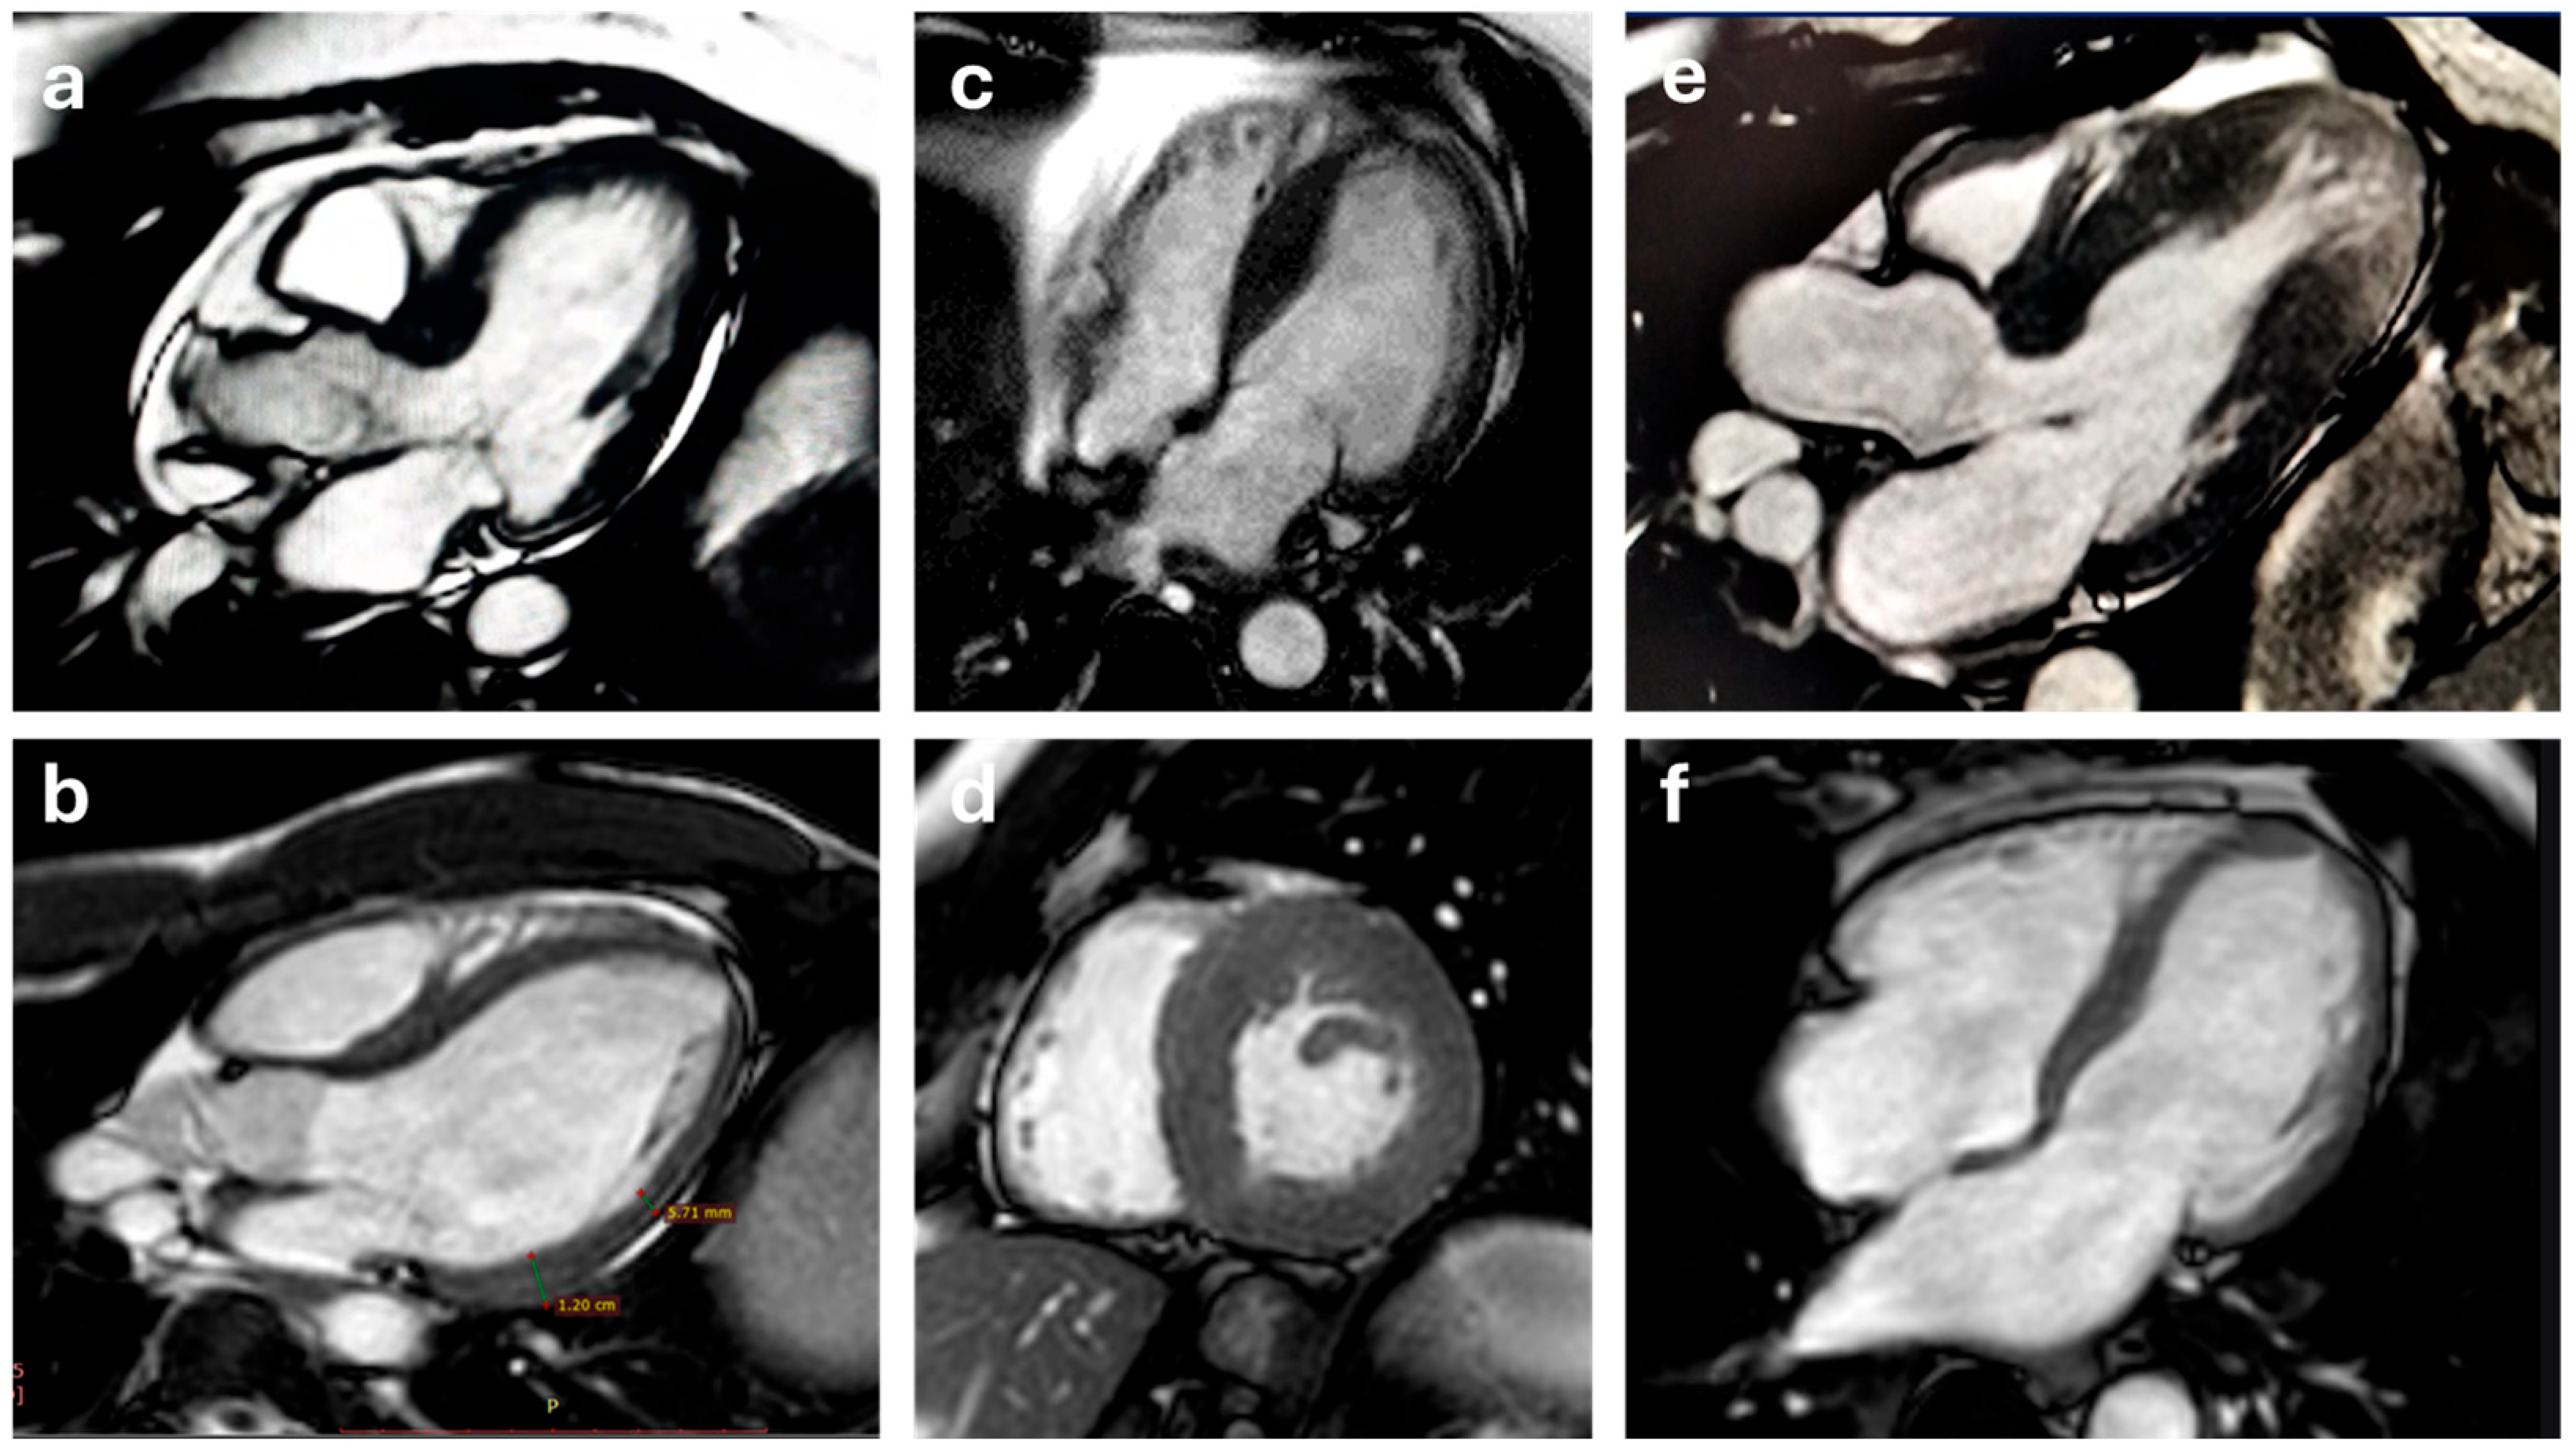

5.1. Cine-MR and Phase-Contrast Velocity Mapping Sequences

5.2. T1 and T2 Mapping

5.3. Late Gadolinium Enhancement